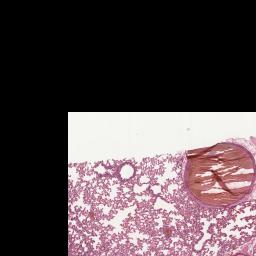

Index of /PathCampVirtualSlides/lung_post-mortem_clot/3